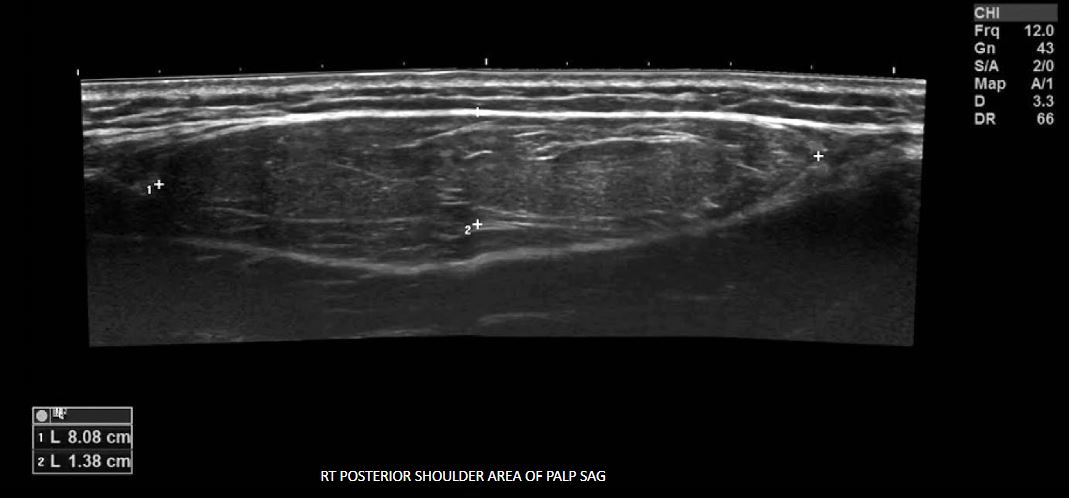

ipoma is the most common soft-tissue tumor. It is composed of adipose (fat) cells and enclosed by a thin, fibrous capsule. Lipomas can originate in any part of the body where normal fat is present, and microscopically, it is impossible to distinguish these benign masses from the normal adipose tissue. Most commonly, lipomas occur in the upper part of the body, specifically under patients' skin on the head, neck, shoulders, arms, and backs. Occasionally they may present in a deep location or originate within a muscle or an organ. They may be solitary or multiple.Lipomas can occur at any age. However, they are commonly found in adults aged 40–60 yearsand are more prevalent in men than in women. Most lipomas are small ovoid tumors weighing only a few grams and measuring less than 5 cm. They typically present as a localized subcutaneous soft mass that causes cosmetic concerns for the patient. Lipomas are generally asymptomatic unless they encroach joints, blood vessels, or nerves. It has been theorized thatlipomas may rarely undergo malignant transformation into a liposarcoma; however, this event has never been convincingly documented. RT POSTERIOR SHOULDER AREA OF PALP SAG20

ipoma usually presents as a painless palpable mass. It is often diagnosed based on the patient's clinical history and the palpation of a well-demarcated, soft, mobile superficial lesion. When a physical examination is inconclusive, ultrasound is the first-line imaging tool used to evaluate the area of concern. Most lipomas have characteristic sonographic features and do not require additional imaging or biopsy.On ultrasound, lipoma commonly appears as a homogeneous, well-defined, ovoid, echogenic tumor without posterior acoustic enhancement measuring less than 5 cm. In large lipomas, fine linear striations may be seen coursing parallel to the skin. Deep lipomas are often isoechoic or hyperechoic to the adjacent muscle and may also present with posterior acoustic enhancement due to the greater acoustic transmission within fat compared to muscle. On color Doppler mode, lipomas typically exhibit no or minimal internal vascularity. Large size (over 5 cm), heterogeneous echotexture, excessive vascularity, and rapid growth are worrisome features for liposarcoma. As a precaution, lesions presenting with these features are often subjected to further imaging or a biopsy.RT POSTERIOR SHOULDER AREA OF PALP TRVLipoma in the posterior aspect of the right shoulder.22